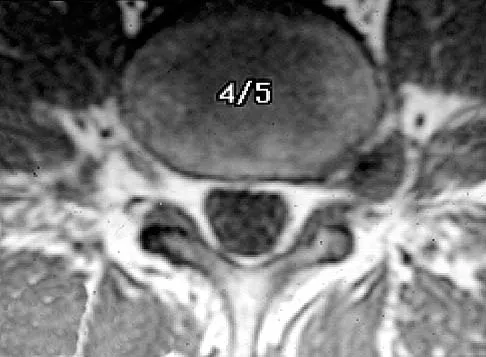

A 30-year-old man has had intermittent swelling of his right ankle for the past 6 months. He denies any history of trauma. Radiographs reveal osteolytic changes on both sides of the joint. An axial CT scan and a T2-weighted MRI scan are shown in Figures 40a and 40b. He undergoes surgical excision. An intraoperative photograph and a biopsy specimen are shown in Figures 40c and 40d. What is the most likely diagnosis?

Explanation